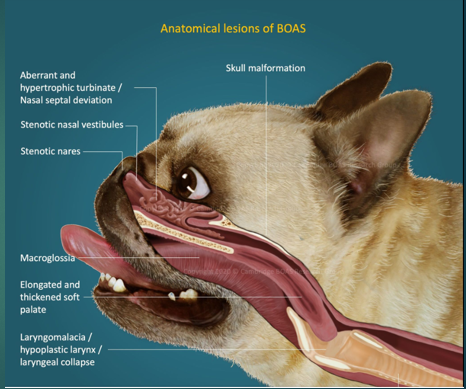

Brachycephalic obstructive airway syndrome in Dogs

Bulldog

Pug

Pekingese

French Bulldog

Boxer

Stenotic nares

Narrowing of the nasal passages, this increases resistance, making breathing in and out more difficult for the paitent

Oversized tongue

Tongue is too big for their moth, can push on soft plate

Elongated soft palate

Effects the epiglottis so can aspirate more easily

Hyperplastic larynx

Overgrowth of soft tissue in the larynx, leading to obstruction

Hypoplastic trachea

Trachea is narrower

Brachycephalic obstructive airway syndrome

The problems we see in these breeds are the consequences of trying to move air with all this increased resistance. To breathe they need to move O2 through the resp tract to the lungs, these issues with the soft tissues that we’ve highlighted cause resistance to air flow, this then increases Resp effort and rate to get more air in, this increases the negative pressure which makes the issue worse – negative pressure caused by them trying to overcome the resistance means that we get more resistance, more swelling of soft tissues and thus more negative pressure. We will often see abdominal effort with BOAS breathing.